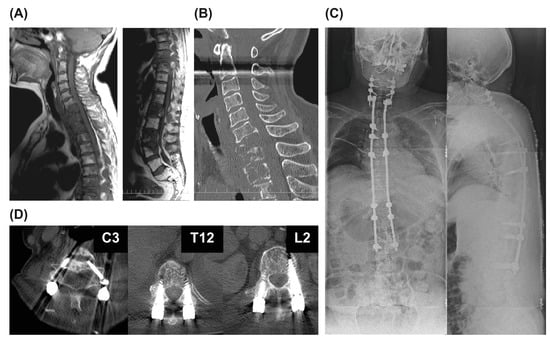

Case Presentation